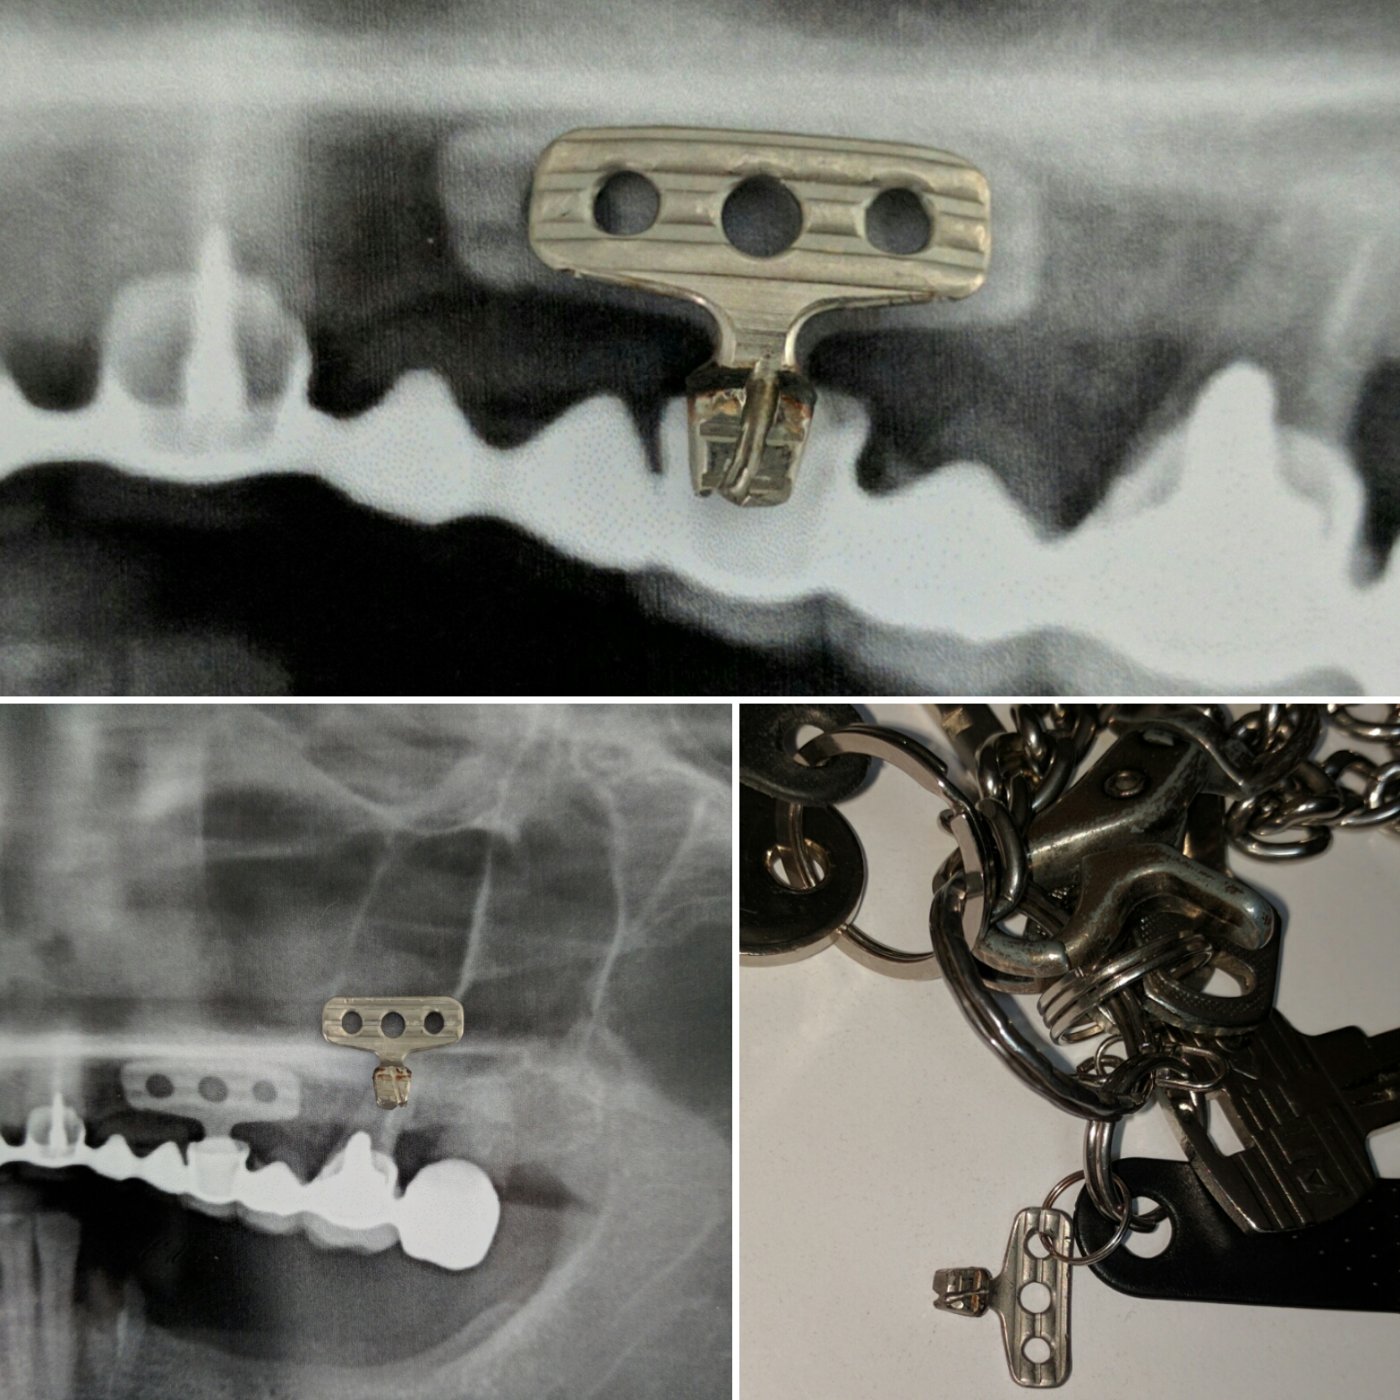

Из навыков: открытый и закрытый синус лифтинг, одномоментная имплантация , расщепление альвеолярного гребня, sausage technique и другая направленная костная регенирация, опыт в работе с титановыми сетками на имплантатах Osstem система Smart Builder, мягкотканная пластика десны, пародонтологические операции. Удаление зубов любой сложности, чтение клкт (3D) и составления рационального плана лечения, стремление расти и развиваться профессионально!